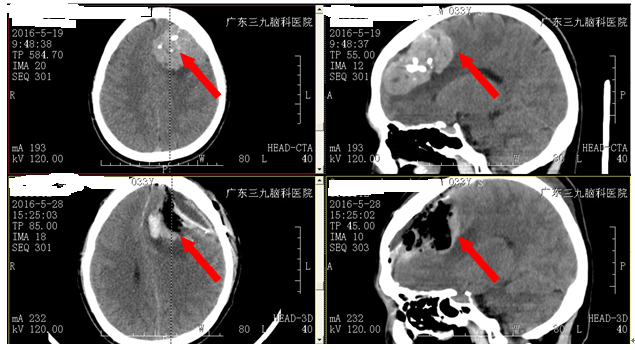

欧阳,男, 33岁,于2个月前无明显诱因出现反复头晕,后突发意识障碍,急诊送往当地医院,行头颅CT及头颅MR提示:左侧额叶占位性病变,考虑脑膜瘤可能性大。为求进一步治疗,来我院就诊,诊断:左侧额叶脑膜瘤。入院后完善相关检查后,由广东三九脑科医院神经外二科林涛主任主刀,在全麻下行“左侧额叶脑肿瘤+ICP探头置入术”,术程进展顺利,显微镜下将肿瘤全切,术后积极给予脱水、补液、预防感染、止血、镇静等一系列治疗后患者头晕情况缓解,康复良好出院。术后诊断与术前诊断一致。术后病理提示:(左侧额部)过渡型脑膜瘤。

上图:术前MR检查,下图:术后MR改变